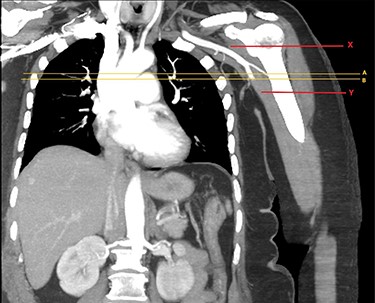

Approximately an hour later, she developed symptoms of pain and weakness to her left arm (the opposite side). Her arm was clinically assessed as cool to touch with a delayed capillary refill with pulses absent. A computed tomography angiogram (CTA) of her left arm was arranged which revealed an abrupt stop in the left axillary artery (Figs 2 and 3) with reconstitution of the vessels in the antecubital fossa. She was taken to theatre for a brachial embolectomy to re-establish blood flow to her acutely ischaemic arm.

CTA of left upper limb in the coronal plane. X—axillary artery with contrast showing flow as evident in transverse imaging (see Fig. 3), patent in the transverse plane marked A. Flow ceases approximately at the level of the plane marked B. Y—axillary artery occluded as shown with contrast absent.

CTA of left upper limb in the transverse plane. B—axillary artery without contrast showing occlusion due to embolism as evident in transverse imaging at B-line (see Fig. 2).